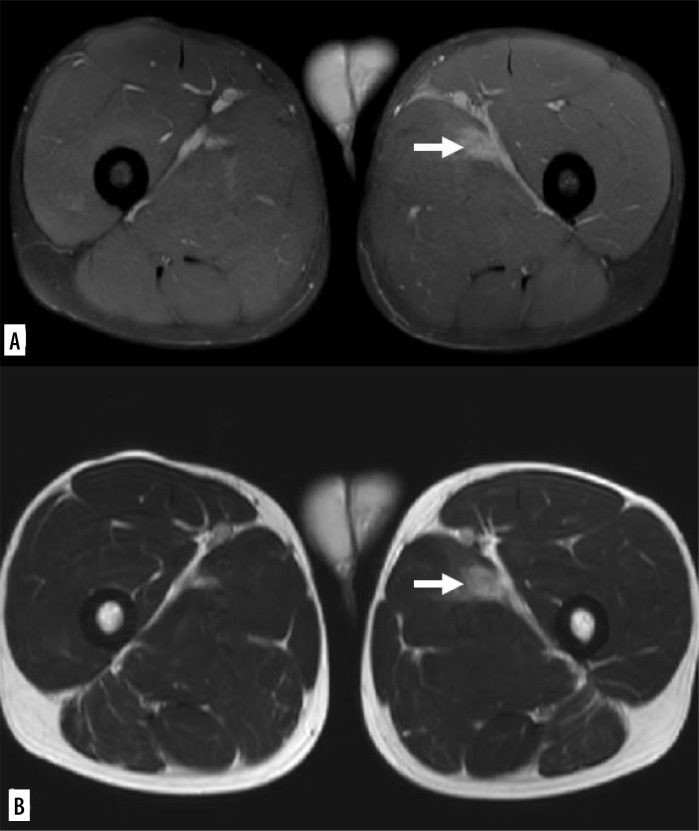

Purpose: Muscle injuries are common in competitive sports. Magnetic resonance imaging (MRI) and ultrasound (US) are the most commonly used methods for evaluating muscle injuries. Several classification systems for muscle injuries have been published. Mueller-Wohlfahrt et al. introduced a new classification system in 2013, currently the most widely used, employing grading to reflect the diverse spectrum of muscle injuries observed in athletes. The differentiation between lesions classified as type 3A (minor partial muscle tear) and 3B (moderate partial muscle tear) remains to be precisely established. In relation to recovery time, we researched possible statistically significant differences.

Material and methods: We conducted a comprehensive analysis of 100 MRI studies that were performed on high-level professional athletes who exhibited clinical signs of lower limb muscle injuries. We selected individuals whose myotendinous or myofascial lesions could be classified as 3A or 3B, based on the Mueller-Wohlfarth (MW) classification. The athletes were then categorised into groups based on the presence or absence of fluid collection at the site of injury. The study's medical practitioner provided data regarding the duration of the injury and the return to sporting activities. Regarding statistical analyses, a linear regression test was conducted to examine the correlation between the variable "fluid collections" and the duration of the injury. Following this, Fisher's t-test or the Mann-Whitney test was applied.

Results: The results of the association between "blood collection" and "duration of injury" revealed a statistically significant correlation. The median value of return to play (RTP) in patients with haemorrhagic collection (median = 29) was significantly higher in comparison with patients without haemorrhagic collection (median = 19), with a difference between the 2 samples of 10 days.

Conclusions: Our study highlights how this distinction could be easily practiced by recognizing the presence of a haemorrhagic collection and how it predominates in determining a worsening of the prognosis and therefore an extension of the RTP. Hence, we can conclude that athletes who do not have blood collection, but only interstitial haemorrhage between fibres can be considered as type 3A, while athletes with interstitial haemorrhage at diagnosis can be considered as type 3B.